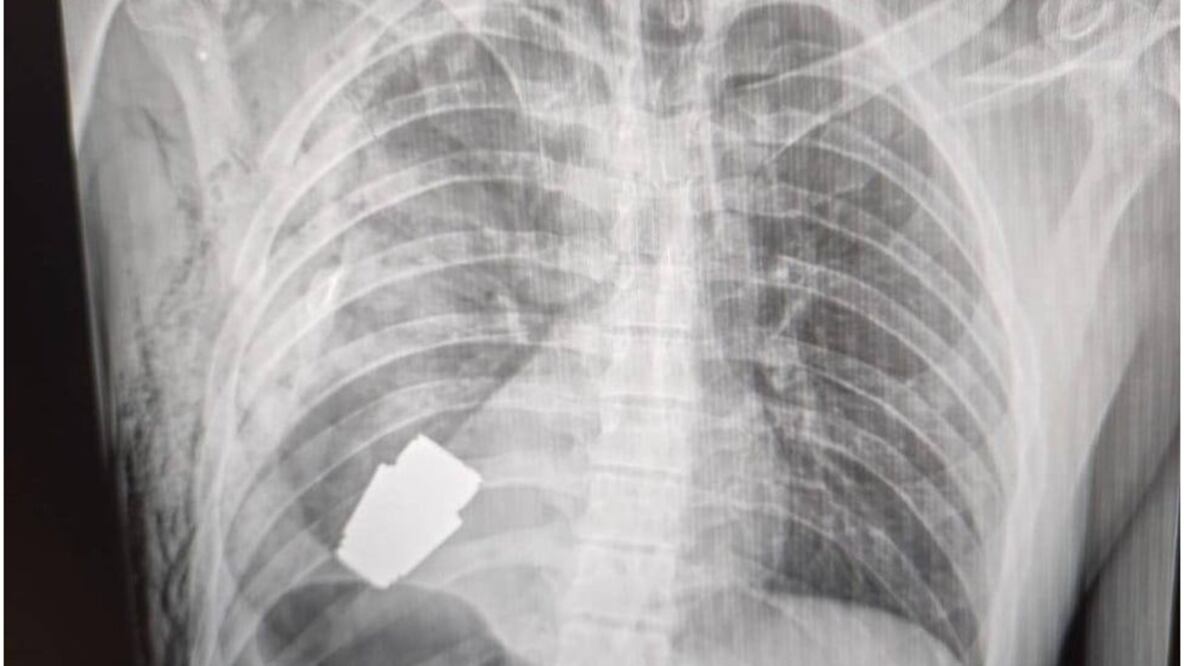

El resultado de la delicada operación fue dado a conocer por la viceministra de Defensa, Hanna Maliar, quien publicó en redes sociales que "no todas las heridas en la zona del corazón son letales".

Agregó que la granada fue extraída bajo la supervisión de dos militares expertos en explosivos para tratar de asegurar la seguridad de los médicos y dar indicaciones para evitar que fuera detonada.

Durante la operación no se pudo utilizar la electrocoagulación, procedimiento común en las cirugías del corazón para evitar que el paciente sufra una hemorragia, por temor a que la corriente eléctrica pudiera detonar la granada.

El fragmento de la granada de fabricación rusa que quedó alojado en el cuerpo del soldado tenía cuatro centímetros de diámetro y pesaba 275 gramos.